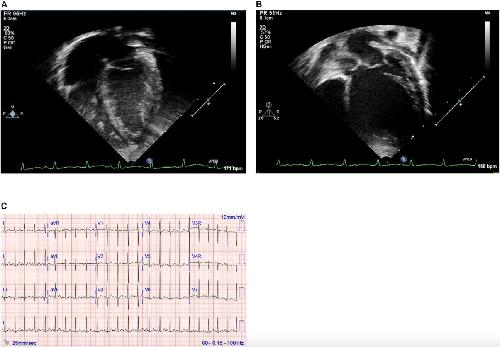

Familial Dilated Cardiomyopathy Associated With a Novel Combination of Compound Heterozygous TNNC1 Variants., Landim-Vieira M, Johnston JR, Ji W, Mis EK, Tijerino J, Spencer-Manzon M, Jeffries L, Hall EK, Panisello-Manterola D, Khokha MK, Deniz E, Chase PB, Lakhani SA, Pinto JR., Front Physiol. January 1, 2019; 10 1612. |